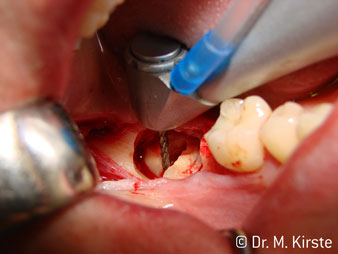

45° ъгъл на наконечника е специално избран поради неговата широка гама от предимства. Колеги, които работят хирургия, и за които този наконечник е главно създаден, скоро ще оценят възможността за ефективна работа в силно ограничени пространства. При екстрахиране на мъдреци, в частност (фиг. 2), няма нужда от голямо разширяване на меката тъкан в областта на бузата (фиг. 3). Дизайнът на главата на наконечника, в съчетание с лекото завъртане на главата по време на препарация, позволява бърза и безопасна работа в ретромоларната област.

Специалният дизайн на лагерите в главата на наконечника гарантира безшумен ход на борера; това прави впечатляващо атравматичен разрез при отделянето на зъба и корена (фиг. 4-9).